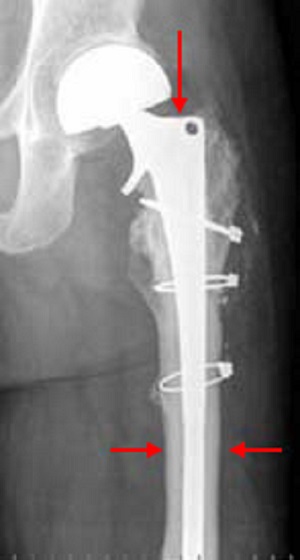

Reconstruction of hip joint after Ewing's sarcoma

This is an X-ray of the same thighbone as the one in the MRI images above. This X-ray was taken 14 years after surgical removal of Ewing sarcoma and reconstruction using a bone graft with an artificial joint replacement.